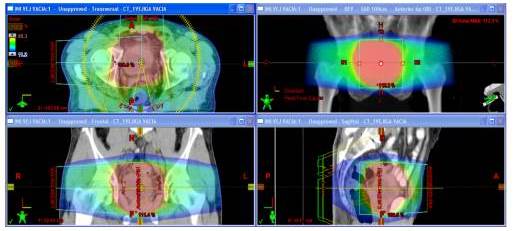

PRÓSTATA

En los casos de tratamientos prostáticos la RAVM es la modalidad primariamente usada. El paciente es colocado de cubito supino y se usan Rayos X de 6 MV. Se emplean arcos axiales con amplitudes de 165° y 195°. El tratamiento dura alrededor de 3 min a diferencia de RTIM el cual toma alrededor de 8 min. A continuación se muestra el plan de tratamiento en planos axial, coronal y sagital para el tratamiento de una lesión prostática.